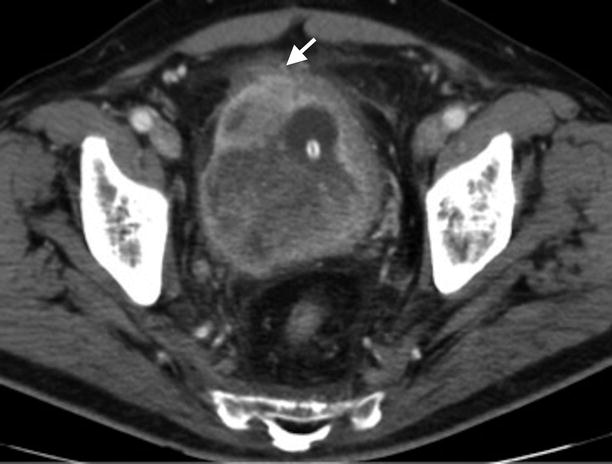

A prolapsed bladder, or cystocele, may occur if tissues that support the bladder weaken or stretch, causing the bladder to descend into the vagina. This is called bladder reconstruction. Complication rates for bladder slings can vary depending on which study you are reading. Surgical complications are potentially encountered with all surgical procedures.